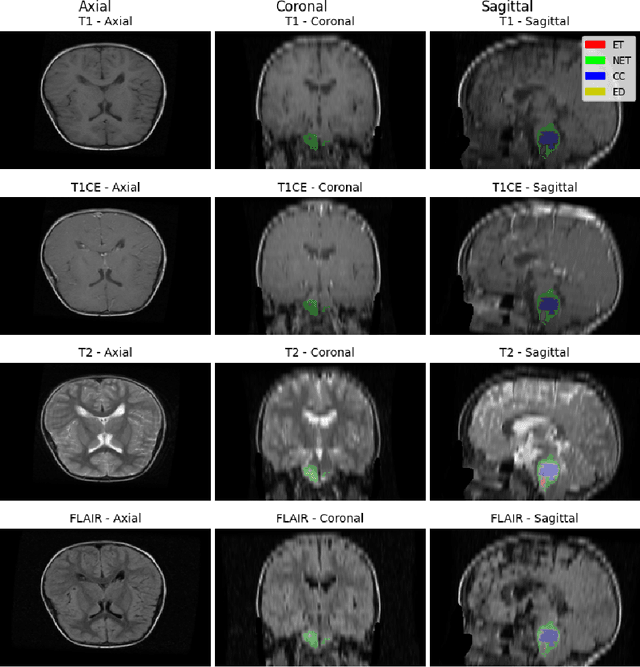

Abstract:Identifying key pathological features in brain MRIs is crucial for the long-term survival of glioma patients. However, manual segmentation is time-consuming, requiring expert intervention and is susceptible to human error. Therefore, significant research has been devoted to developing machine learning methods that can accurately segment tumors in 3D multimodal brain MRI scans. Despite their progress, state-of-the-art models are often limited by the data they are trained on, raising concerns about their reliability when applied to diverse populations that may introduce distribution shifts. Such shifts can stem from lower quality MRI technology (e.g., in sub-Saharan Africa) or variations in patient demographics (e.g., children). The BraTS-2024 challenge provides a platform to address these issues. This study presents our methodology for segmenting tumors in the BraTS-2024 SSA and Pediatric Tumors tasks using MedNeXt, comprehensive model ensembling, and thorough postprocessing. Our approach demonstrated strong performance on the unseen validation set, achieving an average Dice Similarity Coefficient (DSC) of 0.896 on the BraTS-2024 SSA dataset and an average DSC of 0.830 on the BraTS Pediatric Tumor dataset. Additionally, our method achieved an average Hausdorff Distance (HD95) of 14.682 on the BraTS-2024 SSA dataset and an average HD95 of 37.508 on the BraTS Pediatric dataset. Our GitHub repository can be accessed here: Project Repository : https://github.com/python-arch/BioMbz-Optimizing-Brain-Tumor-Segmentation-with-MedNeXt-BraTS-2024-SSA-and-Pediatrics